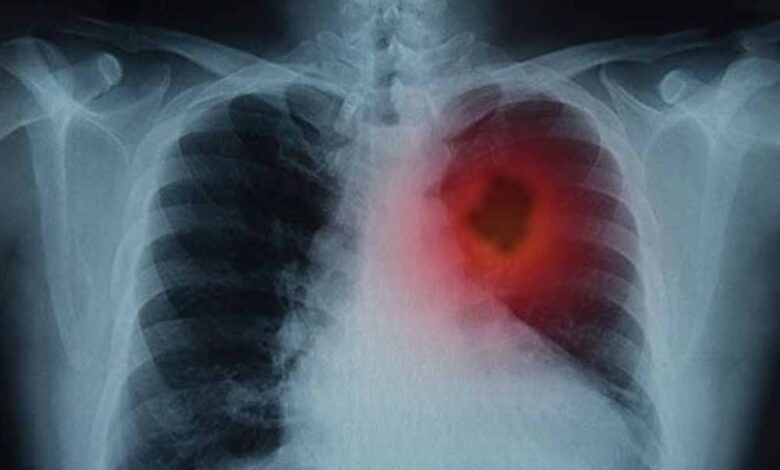

फेफड़ों के कैंसर से जूझ रहे लाखों लोगों के लिए विज्ञान की दुनिया से एक बहुत बड़ी और राहत भरी खबर आई है। दरअसल, वैज्ञानिकों ने एक ऐसा तरीका खोजा है जिससे फेफड़ों के ट्यूमर को उसकी सबसे बड़ी कमजोरी पर वार करके खत्म किया जा सकता है। जी हां, इस शोध के दौरान, उन्होंने एक बेहद जरूरी प्रोटीन की पहचान की। बता दें, यह प्रोटीन कैंसर कोशिकाओं को 'मरने' से बचाता है। ऐसे में, शोधकर्ताओं का कहना है कि अगर इस खास प्रोटीन की गतिविधि को रोक दिया जाए, तो कैंसर कोशिकाएं खुद-ब-खुद नष्ट होने लगती हैं और ट्यूमर सिकुड़ जाता है।

हाल ही में शोधकर्ताओं ने फेफड़ों के कैंसर की एक महत्वपूर्ण कमजोरी का पता लगाया है- एक ऐसा प्रोटीन, जिसे रोक दिया जाए तो कैंसर कोशिकाएं खुद को ही नष्ट करने लगती हैं। यह खोज न सिर्फ इलाज के नए रास्ते खोलती है, बल्कि भविष्य में ऐसे कई मरीजों के लिए जीवनदायिनी साबित हो सकती है, जिन्हें अब तक सीमित विकल्प ही उपलब्ध थे।